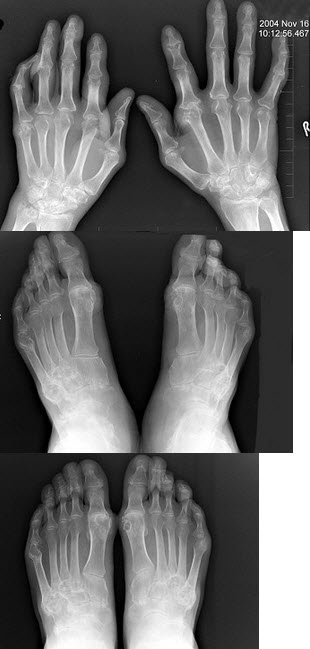

244、单项选择题

女,50岁,手指关节肿痛,晨僵,结合图像,最可能诊断是()

A.关节结核

B.牛皮癣性关节炎

C.痛风性关节炎

D.类风湿关节炎

E.Reiter综合征